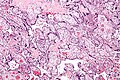

Microscopic

Features:

- Acellular eosinophilic material around formed villi.

- Obliteration of intervillous space.

- Intervillous distance increased vis-a-vis normal - key feature.

Notes:

- Nuclei of villi are usually preserved.

- Villi may have secondary infarction, i.e. there may be nuclear destruction (karyolysis, karyorrhexis, pyknosis).

DDx:

- Placental infarction - loss of nuclei in the villi (below the edge of the lesion).

- Massive perivillous fibrin deposition (maternal floor infarct).